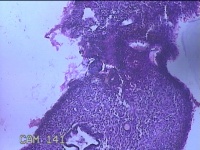

宫腔内容物

性别

女

年龄

42岁

临床诊断

异常子宫出血;贫血

一般病史

阴道流血半个月。

标本名称

大体所见

灰白暗红色不规则碎组织2.3x2x0.8cm一堆。

图1